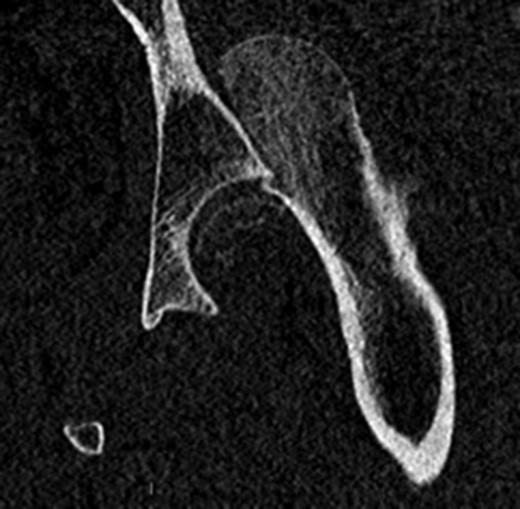

A fit and well man in his 40s had fallen while hiking up a steep hill. He complained of immediate onset, severe left hip pain and inability to move. He was airlifted to our hospital and was found to have shortened externally rotated left leg. Plain X-rays were performed in the emergency department (Fig. 1) identifying isolated fracture–dislocation of the left hip. Computed tomography (CT) was performed while en route to theatre (Figs 2 and 3).

AP radiograph of left hip showing fracture–dislocation of femoral head.

Due to the time involved in the airlift extraction, the hip was dislocated for ~5–6 h. He was attended to by the on-call Consultant Orthopaedic Surgeon, and under general anaesthetic, the hip was reduced with no particular difficulty. The case was referred to the department hip specialist. A further CT scan was performed to assess the position of the fracture to aid in pre-op planning.